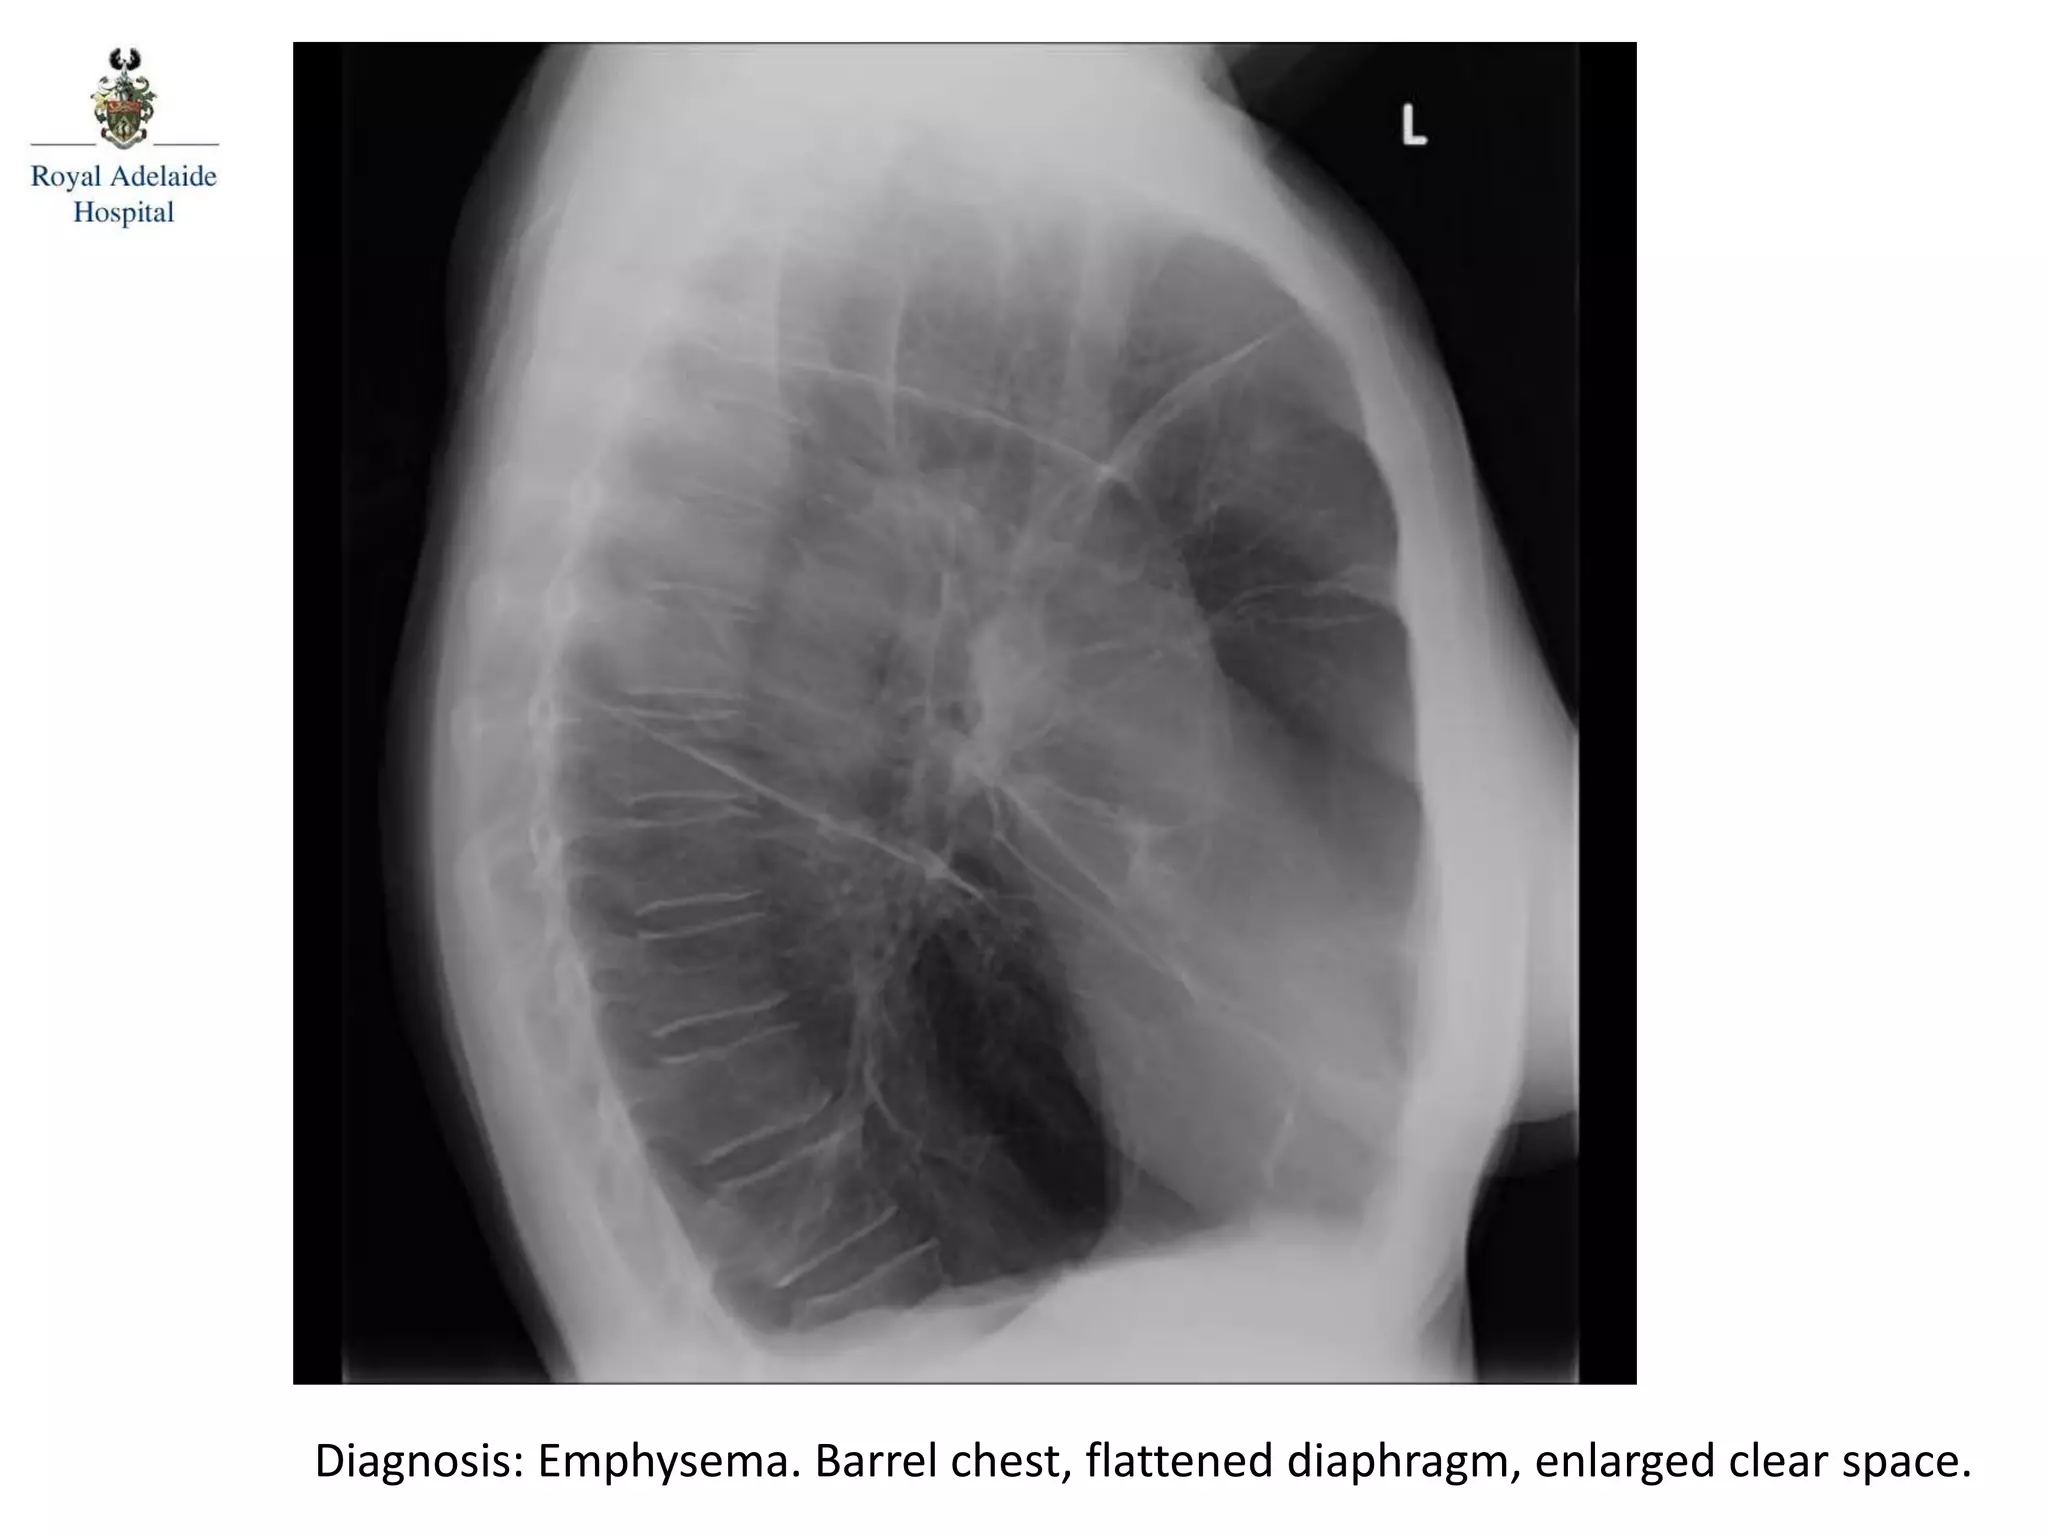

Diagnosis: Emphysema. Barrel chest, flattened diaphragm, enlarged clear space.